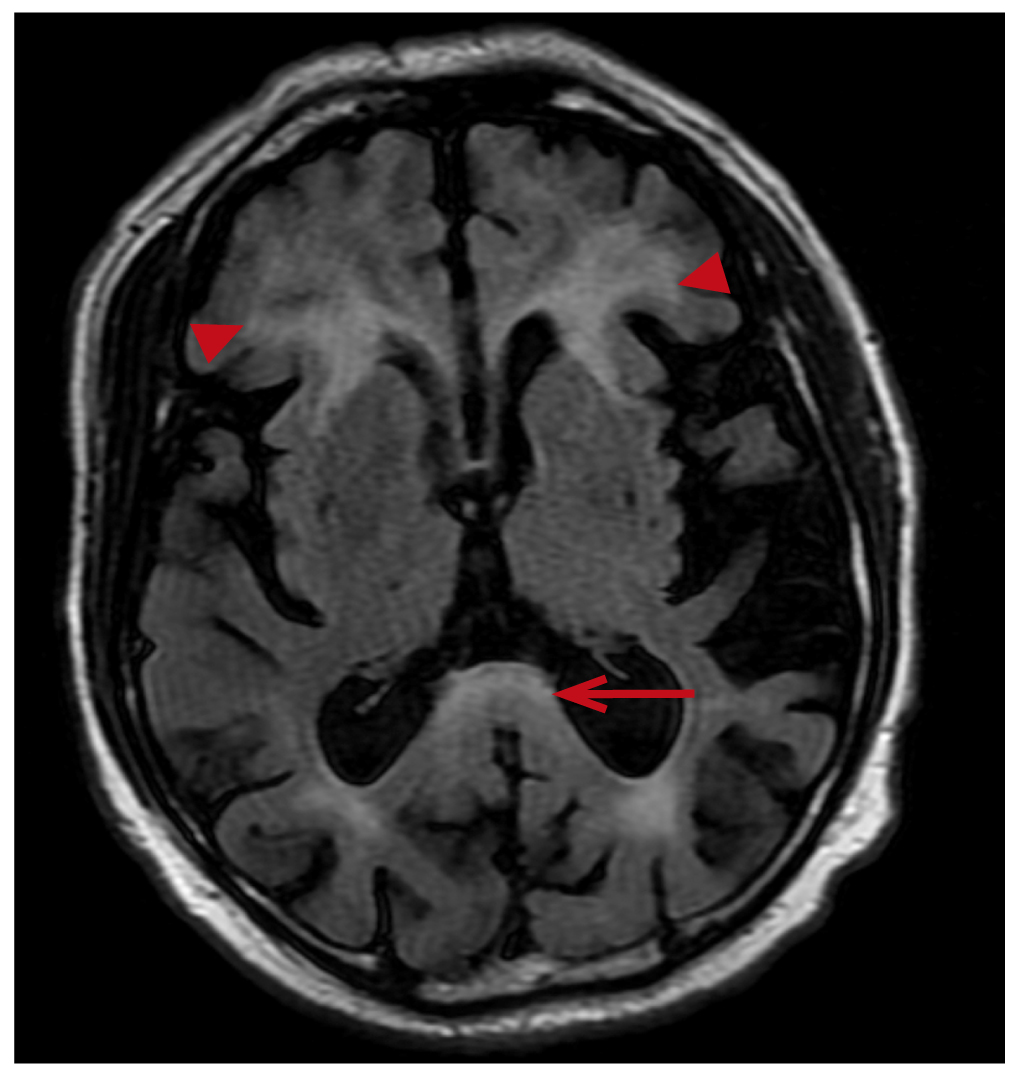

Brain MRI (05.02.2025): the observations include a diffuse inhomogeneous increase of the MRI-signal from white matter of the brain for Т2- and Т2-FLAIR (Fluid-Attenuated Inversion Recovery) images with spreading to the middle cerebellar peduncles and the cerebellum hemispheres, with linear-stellar increase of the MRI-signal for the DWI mode, with no signs of diffusion restriction. Conclusion: “MRI signs corresponding to the manifestations of the neurodegenerative diseases (FXTAS). Diffuse cerebral atrophy grade I” (Fig. 2, 3).

Fig. 2. Symmetrical foci of high signal in the T2-weighted images at the level of the middle cerebellar peduncles.

Fig. 3. Hyperintensity in the area of the splenium of corpus callosum in a series of FLAIR (long arrow), additional finding — foci of symmetrical periventricular leukoaraiosis near the anterior horns (short arrows).